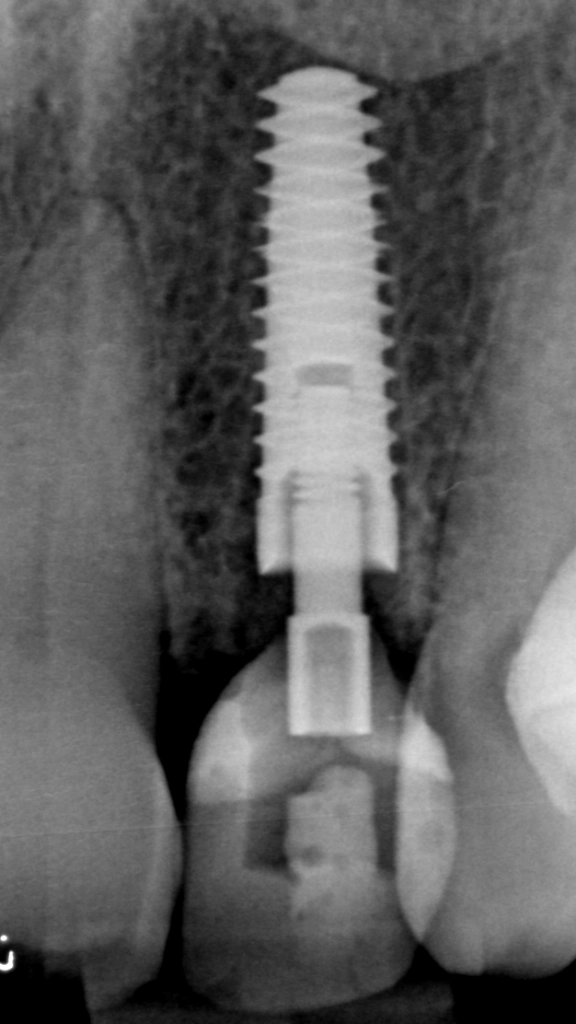

De röntgenfoto laat een mooie positie zien. (Op de foto lijkt deze niet precies in het midden te staan, maar dit is absoluut vertekening door de inzetrichting van de röntgenbuis). Aan weerszijden van het implantaat is de tandkas van de oude wortel goed zichtbaar. De tijdelijke stift is niet zichtbaar op röntgenfoto's.